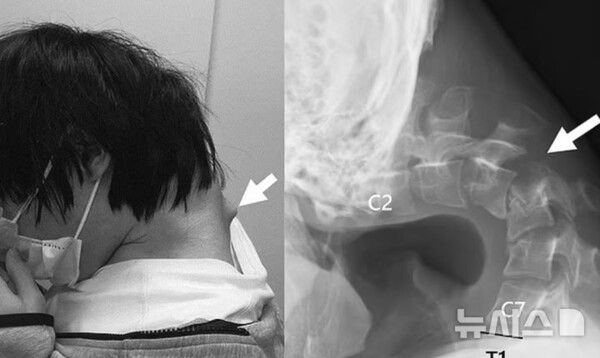

장시간 스마트폰 사용으로 인해 목뼈가 꺾여 고개를 제대로 들 수 없게 된 20대 남성의 사례가 공개됐다.

여러 검사 끝에 의료진은 남성의 목뼈가 심하게 뒤로 젖혀져 있는 상태이며, 일부 목의 척추뼈는 비정상적으로 이탈한 것을 발견했다.

의료진은 이 남성이 수년간 바닥을 보며 스마트폰 게임에 몰두한 결과, 경추에 정상적인 하중이 지속적으로 가해졌다고 판단했다.

특히 목을 깊이 숙인 상태에서 장시간 스마트폰을 사용하는 습관이 원인이 됐다고 의료진은 분석했다.

이후 의료진은 척추 일부를 절제하고, 금속 나사와 막대를 삽입해 경추를 고정하는 수술을 진행했다.

수술 6개월 후 남성은 정상적으로 고개를 들 수 있게 됐으며, 음식을 삼키는 데에도 문제가 없었다.